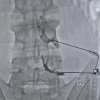

VAN - Van'da yaşam kalitesini olumsuz yönde etkileyen kronikleşmiş ağrı şikayeti olan hastalar, Van Eğitim ve Araştırma Hastanesi bünyesinde hizmet veren Algoloji (Ağrı) Polikliniğinde tedavi oluyor. Doğu Anadolu Bölgesi'nde yaklaşık 3 milyon hastaya hizmet veren Van Eğitim ve Araştırma Hastanesi, kronikleşmiş ağrı şikayeti olan hastalara da umut oluyor. Hastane bünyesinde iki uzman hekimle hizmet veren Algoloji Polikliniği, yaşam kalitesini olumsuz etkileyen ağrıları ortadan kaldırmak üzere tedavi çalışması yürütüyor. Algoloji Polikliniği, genellikle kanser ağrıları, nevraljiler, kas-iskelet sistemi ağrıları, boyun ağrıları, omuz-kol ağrıları, sırt ağrıları, bel-bacak ağrıların tedavisiyle ilgileniyor. "Hastalarımız ağrılarla yaşamak zorunda değil" Konuya ilişkin konuşan Hastane Başhekimi Doç. Dr. Remzi Sarıkaya, Algoloji Polikliniğin tüm imkanlara sahip olduğunu belirtti. Poliklinik hizmetinin yanı sıra girişimsel hizmetlerin de yapıldığını ifade eden Başhekim Sarıkaya, "Kronik ağrı çeken hastalarımıza her türlü işlem yapılmaktadır. Bizler bunu önemsiyoruz. Çünkü kronik ağrılar, insanın hayat kalitesini bozan önemli semptomlardan biridir. Kronik ağrıları olan hastalarımız artık bu ağrılarla yaşamak zorunda değiller. Bu rahatsızlığı olanlar algoloji uzmanlarımıza başvurabilirler. Buraya başvuran hastalarımız gerekli tedavileri olabilirler" dedi. "Hastalarımızın büyük sıklıkla ağrılarını dindirebiliyoruz" Algoloji Uzmanı Dr. Ayşegül Akyüz Yıldırım ise özellikle kronik ağrıları, kanser, bel fıtığı, boyun fıtığı ya da kronik bel-boyun ağrıları, baş ağrısı, migren, trigeminal nevralji, küme baş ağrısı, eklem ağrıları, fibromyalji, fantom ağrısı gibi şiddetli ağrı şikayeti olan hasta grubunun kendilerine başvurduğunu belirterek, "Poliklinikte yaptığımız işlemler var, bir de ameliyathanede yapılan işlemler var. Ameliyathanede floroskopi ya da ultrason eşliğinde işlemlerimizi gerçekleştiriyoruz. Görüntüleme eşliğinde ve steril şartlarda bu işlemleri yapıyoruz. Bu yüzden hastanın iyi bir uzman tarafından değerlendirilmesi çok önemlidir. Hastalarımızın büyük sıklıkta ağrıları dindirebiliyoruz. Yüzde 50'lik bir ağrı azalması bile sağlayabilirsek hastanın hayat kalitesini artırmış oluyoruz" diye konuştu. "Hastanın ameliyat olmasına ve ilaç kullanmasına gerek kalmıyor" Medikal tedaviden fayda görmeyen hastalara girişimsel tedaviler uyguladıklarını dile getiren Algoloji Uzmanı Dr. Gökhan Sucu da "Bizim yaptığımız işlemler hastaların ağrılarını geçirmek bir yana, orayı tedavi de ediyor. Kalıcı bir ağrının geçmesine vesile oluyor. Bizim yaptığımız aslında bel fıtığının ameliyatsız bir yöntemidir. Fıtığın sinire bastığı bölgeye iğneyle girip, orada ilaçla radyofrekans tedavisi uyguluyoruz. Bu şekilde fıtık biraz geri çekilme yaşayıp sinire baskısı ortadan kalkıyor ve ağrısı bu şekilde geçmiş oluyor. Bu tedaviyle hastanın ameliyat olmasına ve ilaç kullanmasına gerek kalmıyor. Daha çok bize beyin cerrahi, ortopedi, fizik tedavi ve nöroloji bölümlerinden hastalar geliyor. Sebebi bilinmeyen ve geçmeyen, medikal tedaviden fayda görmeyip ağrı çeken hastalar geliyor. Biz de girişimsel tedavilerimizle son noktada ağrıları geçirmeye çalışıyoruz" şeklinde konuştu.